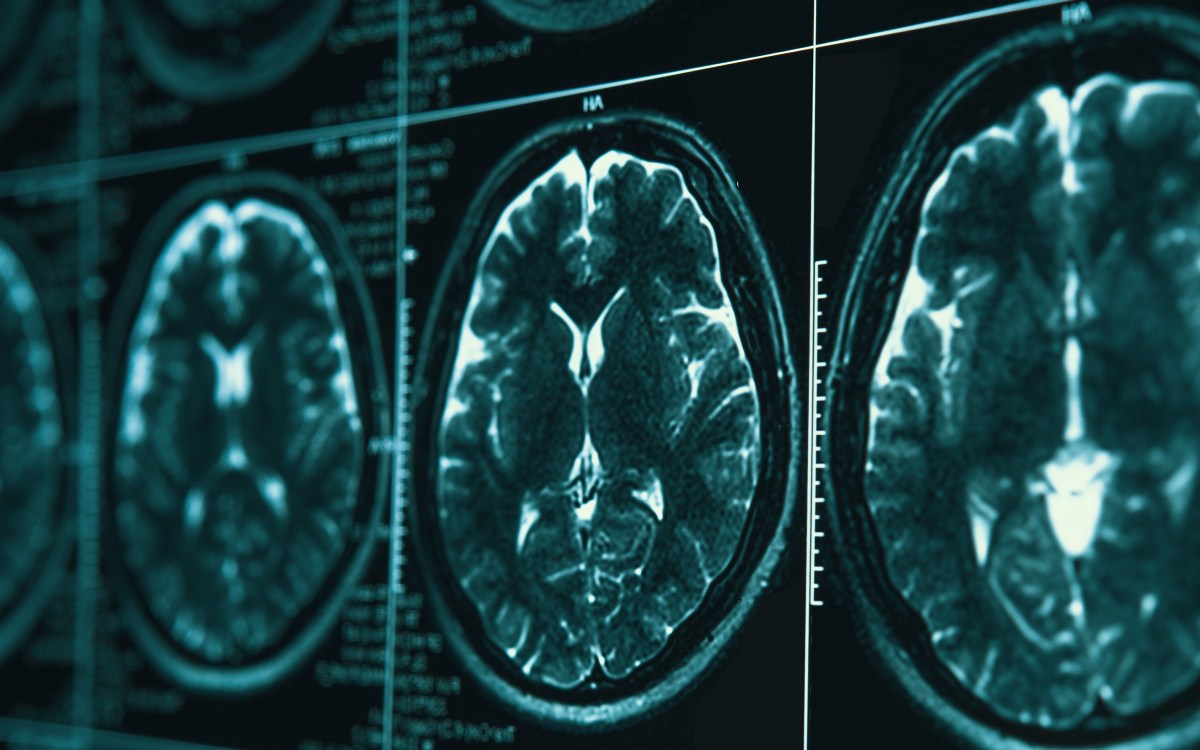

HealthMaking real gains in war on Alzheimer’s

Researchers hope new technologies, approaches usher in era of effective treatment for incurable disease amid urgency of ‘silver tsunami’